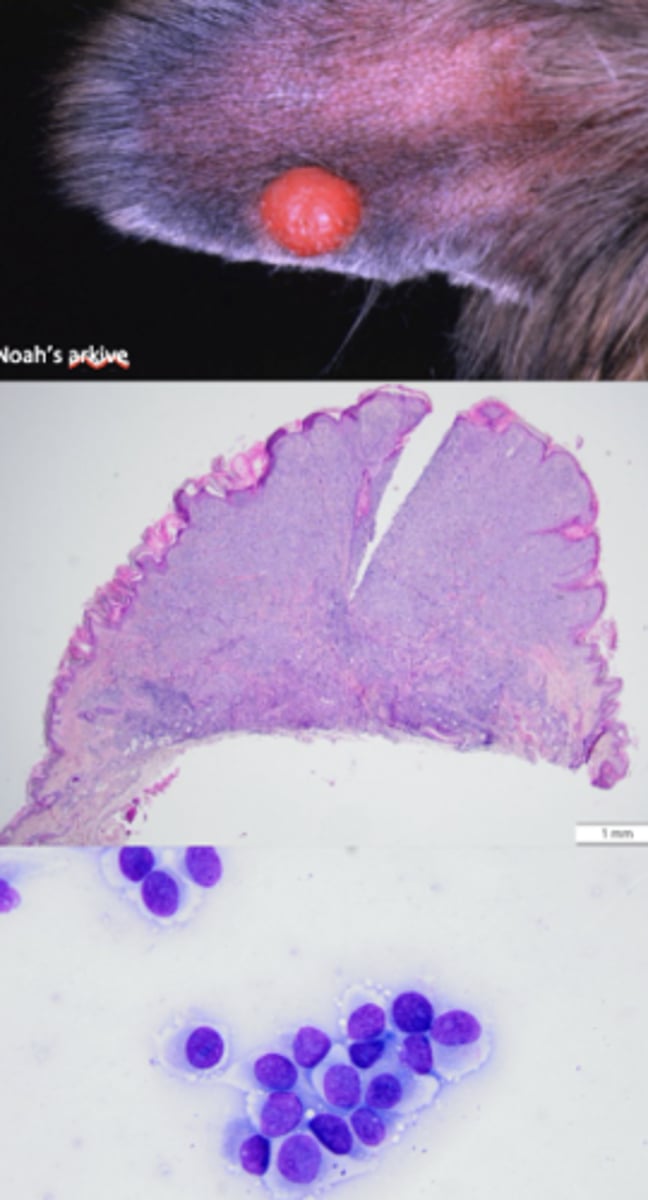

Mast cell tumor !!

-granulated

-red

What has caused this gross appearance of this liver?

Mast cell tumor

What kind of round cell tumor is this?